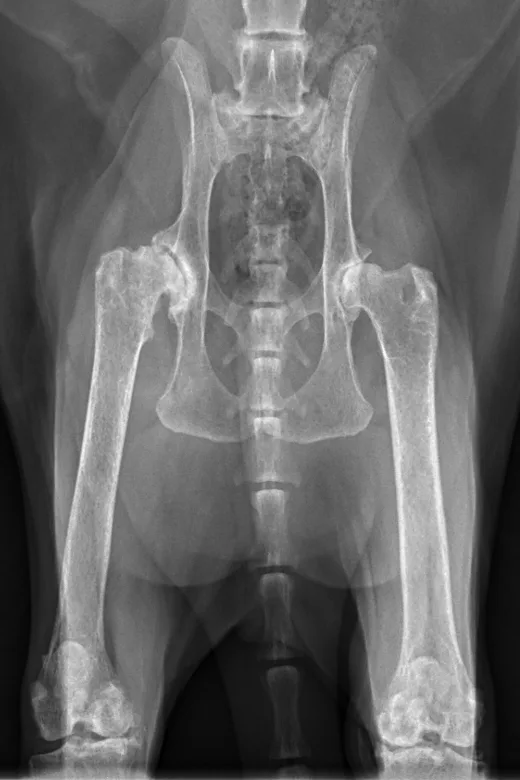

Radiographs taken by the referring clinician showed a shallow right acetabulum with decreased coverage of the femoral head and secondary changes, including a sclerotic acetabular rim, smoothly marginated periosteal proliferation along the cranial and caudal pillars of the acetabulum, flattening of the right femoral head, thickening of the femoral neck, and mild craniodorsal subluxation. The left coxofemoral joint was congruent but had mild changes with osteophytes along the cranial acetabular margin. There was a mild amount of spondylosis deformans at L6-L7 and L7-S1. Radiographs of the stifles showed subchondral bone sclerosis of both medial femoral condyles and medial tibial condyles. Osteophytes and enthesophytes were present along the distal femurs and proximal tibiae. A large amount of amorphous periarticular new bone was located within and adjacent to the craniomedial aspects of the stifle joints and just proximal to the tibial eminences. Radiographic diagnoses at that time were moderate, right-sided, coxofemoral degenerative joint disease with subluxation of the femoral head; mild, left-sided, coxofemoral degenerative joint disease with no evidence of subluxation; and severe, bilateral stifle degenerative joint disease.At the referral clinic, 8.5 months after initial presentation, Max was sedated, and repeat ventrodorsal and orthogonal lateral pelvic radiographs were obtained to evaluate progression or change (Figure).

Ventrodorsal and right lateral radiographic images of feline stifle demonstrating arthritic changes.

FIGURE 1

Ventrodorsal and lateral pelvic radiographs showing severe osteophyte formation along the right femoral head and neck that caused effacement of the trochanteric fossa. The acetabulum is shallow due to remodeling and osteophyte formation. Mild osteophyte formation remains along the left femoral head and neck, as well as moderate osteophyte formation along the acetabulum. Caudal lumbar spondylosis deformans is unchanged from initial radiographic findings. Rounded, angular mineral bodies are present bilaterally in the stifle joints with moderate concurrent periarticular osteophyte formation. Short, linear mineral bodies can be seen in the soft tissues of the right caudal crus.

Although findings were unchanged from previous radiographs, OA in the right hip appeared mildly progressed.